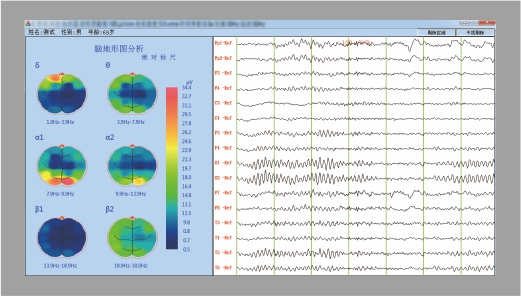

棘波分析                                                                                地形图分析

具备棘波分析功能,可自动识别并标记出癫痫病理波,                                                  可对任意病例数据进行地形图分析并显示成二维三视地形图

24小时数据5分钟内分析完给出分析结果,方便医生判断。                                          使医生直观地了解脑区中的异常放电状况。